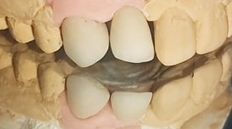

Prosthetic conception

(Figures 13–20) All ceramic crown with a zirconia framework would provide an acceptable aesthetic result. Zirconia framework always requires a try-in step to confirm fit, insertion, retention, and mostly the space left for cosmetic ceramic. After veneering with feldspathic ceramic, and intraoral checking, crowns were glazed, then cemented: A good aesthetic integration was observed: respect of the shape, volume and color of the tooth compared to its counterpart with well distributed diastemas.

Figure 15 A try-in of the Zirconia framework.

Figure 16 Ceramic stratification was performed in the laboratory.

Figure 17 A final try-in, of the zirconia ceramic crowns.